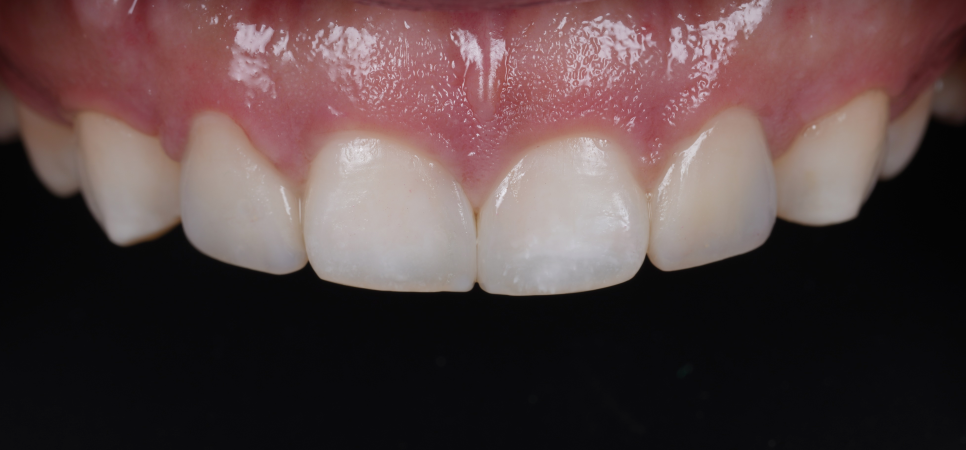

2주 뒤 내원하셔서 환자분이 가운데 앞니 이야기를 꺼내셨어요.

“이 사이 벌어진 것도 치료하고 싶어요.”

사이에 벌어진 공간도 자연스럽게 메워드렸습니다.

촬영일 : 260103

미세한 부분까지 조정해 드렸어요.

레진은 치료도 중요하지만 그 이후도 정말 중요해요.

치료 직후에는 괜찮아 보여도 잇몸이 가라앉으면서 레진 경계가 느껴질 수 있고 말할 때, 웃을 때, 혀로 만졌을 때 미세한 불편이 생길 수 있어요.

그래서 이번 앞니도 2주 간 경과를 체크했어요.

“손톱이 살짝 걸리는 느낌이 있어요.”

“말할 때 입술이 조금 누르는 듯한 느낌이 들어요.”

그때마다 조금씩 다듬고 필요한 부분만 미세하게 조정했어요.

완벽히 매끈하게 만드는 것보다 내 입에서 자연스럽게 느껴지는 상태가 더 중요하니까요.

촬영일 : 251203 / 251220